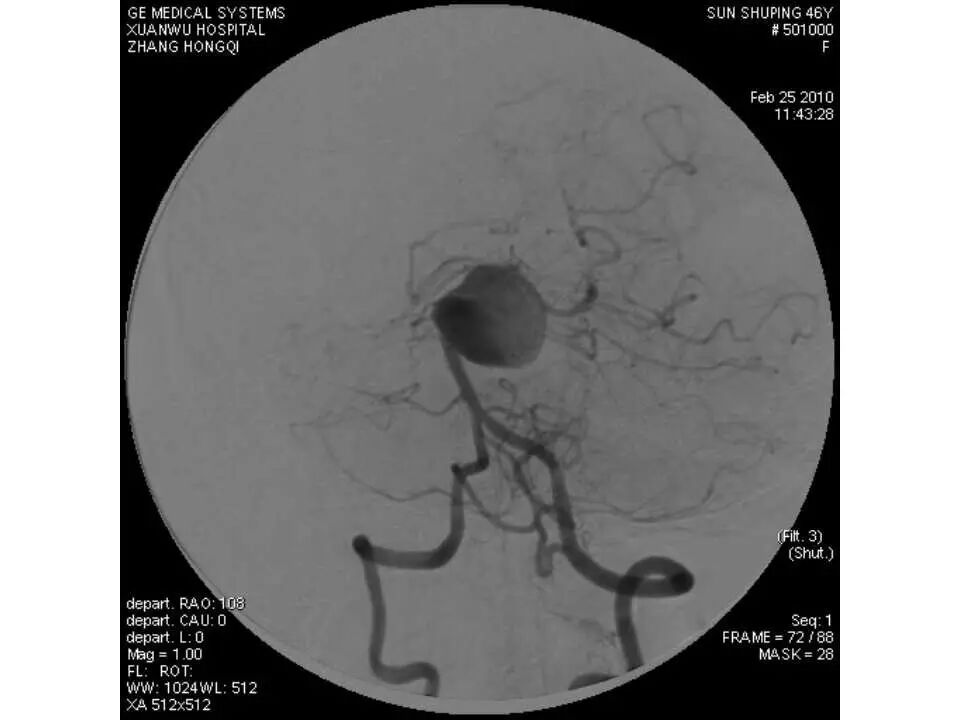

今天为大家分享的是“强生医疗CNV-神经介入专栏”第十五期,由首都医科大学宣武医院何川教授带来的“颅内动脉瘤介入治疗”精彩讲课视频及PPT,欢迎观看、阅读。文章仅代表作者个人观点,如有不同见解,欢迎同道斧正!

何川 ,首都医科大学宣武医院副主任医师,中国医师协会神经介入专业委员会常务委员,长期从事脑血管病和脊髓血管病的手术及介入治疗和相关研究工作。首都医科大学神经外科博士,师从于中国神经介入开创人凌锋教授;日本东北大学医院脑血管病治疗科博士后,师从于日本国脑血管病血管内治疗的开创者高桥教授。